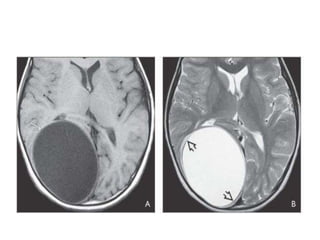

Echinococcosis

– Larval stage- hydatid cyst

– Cerebral hydatid- seen in only 2% cases

– Imaging

• Single thin walled spherical CSF density cyst

• Large cystic lesion lying subcortically in middle cerebral

territory of parietal area (can reach large size often

over 6 cm in diameter).

• No edema or enhancement or adjacent calcification.

• Enhancement and perilesional edema are seen only if

the cyst is superinfected.